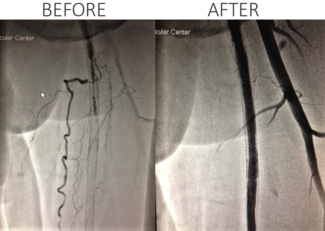

Bibhav Poudel, BS; Atharva Dhole, MD; Grace Pyon, BS; Maria Litzendorf, MD; Scott Brannan, MD; Nikhil Patel, MD

The authors present the case of a diabetic patient with a right plantar hallux ulceration, CTO of arteries supplying the right hallux on angiogram despite benign non-invasive testing, and the effects of revascularization in the region.